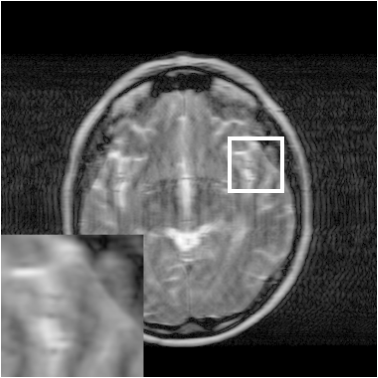

Figure 7: Reconstruction results for 20% variable density sampling. (a) Original. (b)-(h) Reconstructed images. (i)-(n) The errors of six CSMRI methods.

As shown in Figs. 7, 8 and 9, Sparse MRI and DLMRI have a lot of unpleasant artifacts, Residual learning and U-net can eliminate most of artifacts, but are not ideal for restoring image details. However, the proposed method can reconstruct better MR images, which outperforms other competitive methods in visualization of structures reconstruction and artifacts removal. Meanwhile, we can see from the absolute error residuals for three sampling experiments that the proposed MDN algorithm restores a finer detail structure than other algorithms. Moreover, we present the PSNR and SSIM values in Table I for different algorithms, sampling masks and sampling rates. It is demonstrated that the proposed method provides better reconstruction performance and visual results than other competitive methods. We can also see the obvious improvement of all algorithms over zero-filling both in visualization. In particular, a higher SSIM value of Sparse MRI appears when using 30% variable density random sampling, however, Sparse MRI generates more artifacts than the proposed MDN.